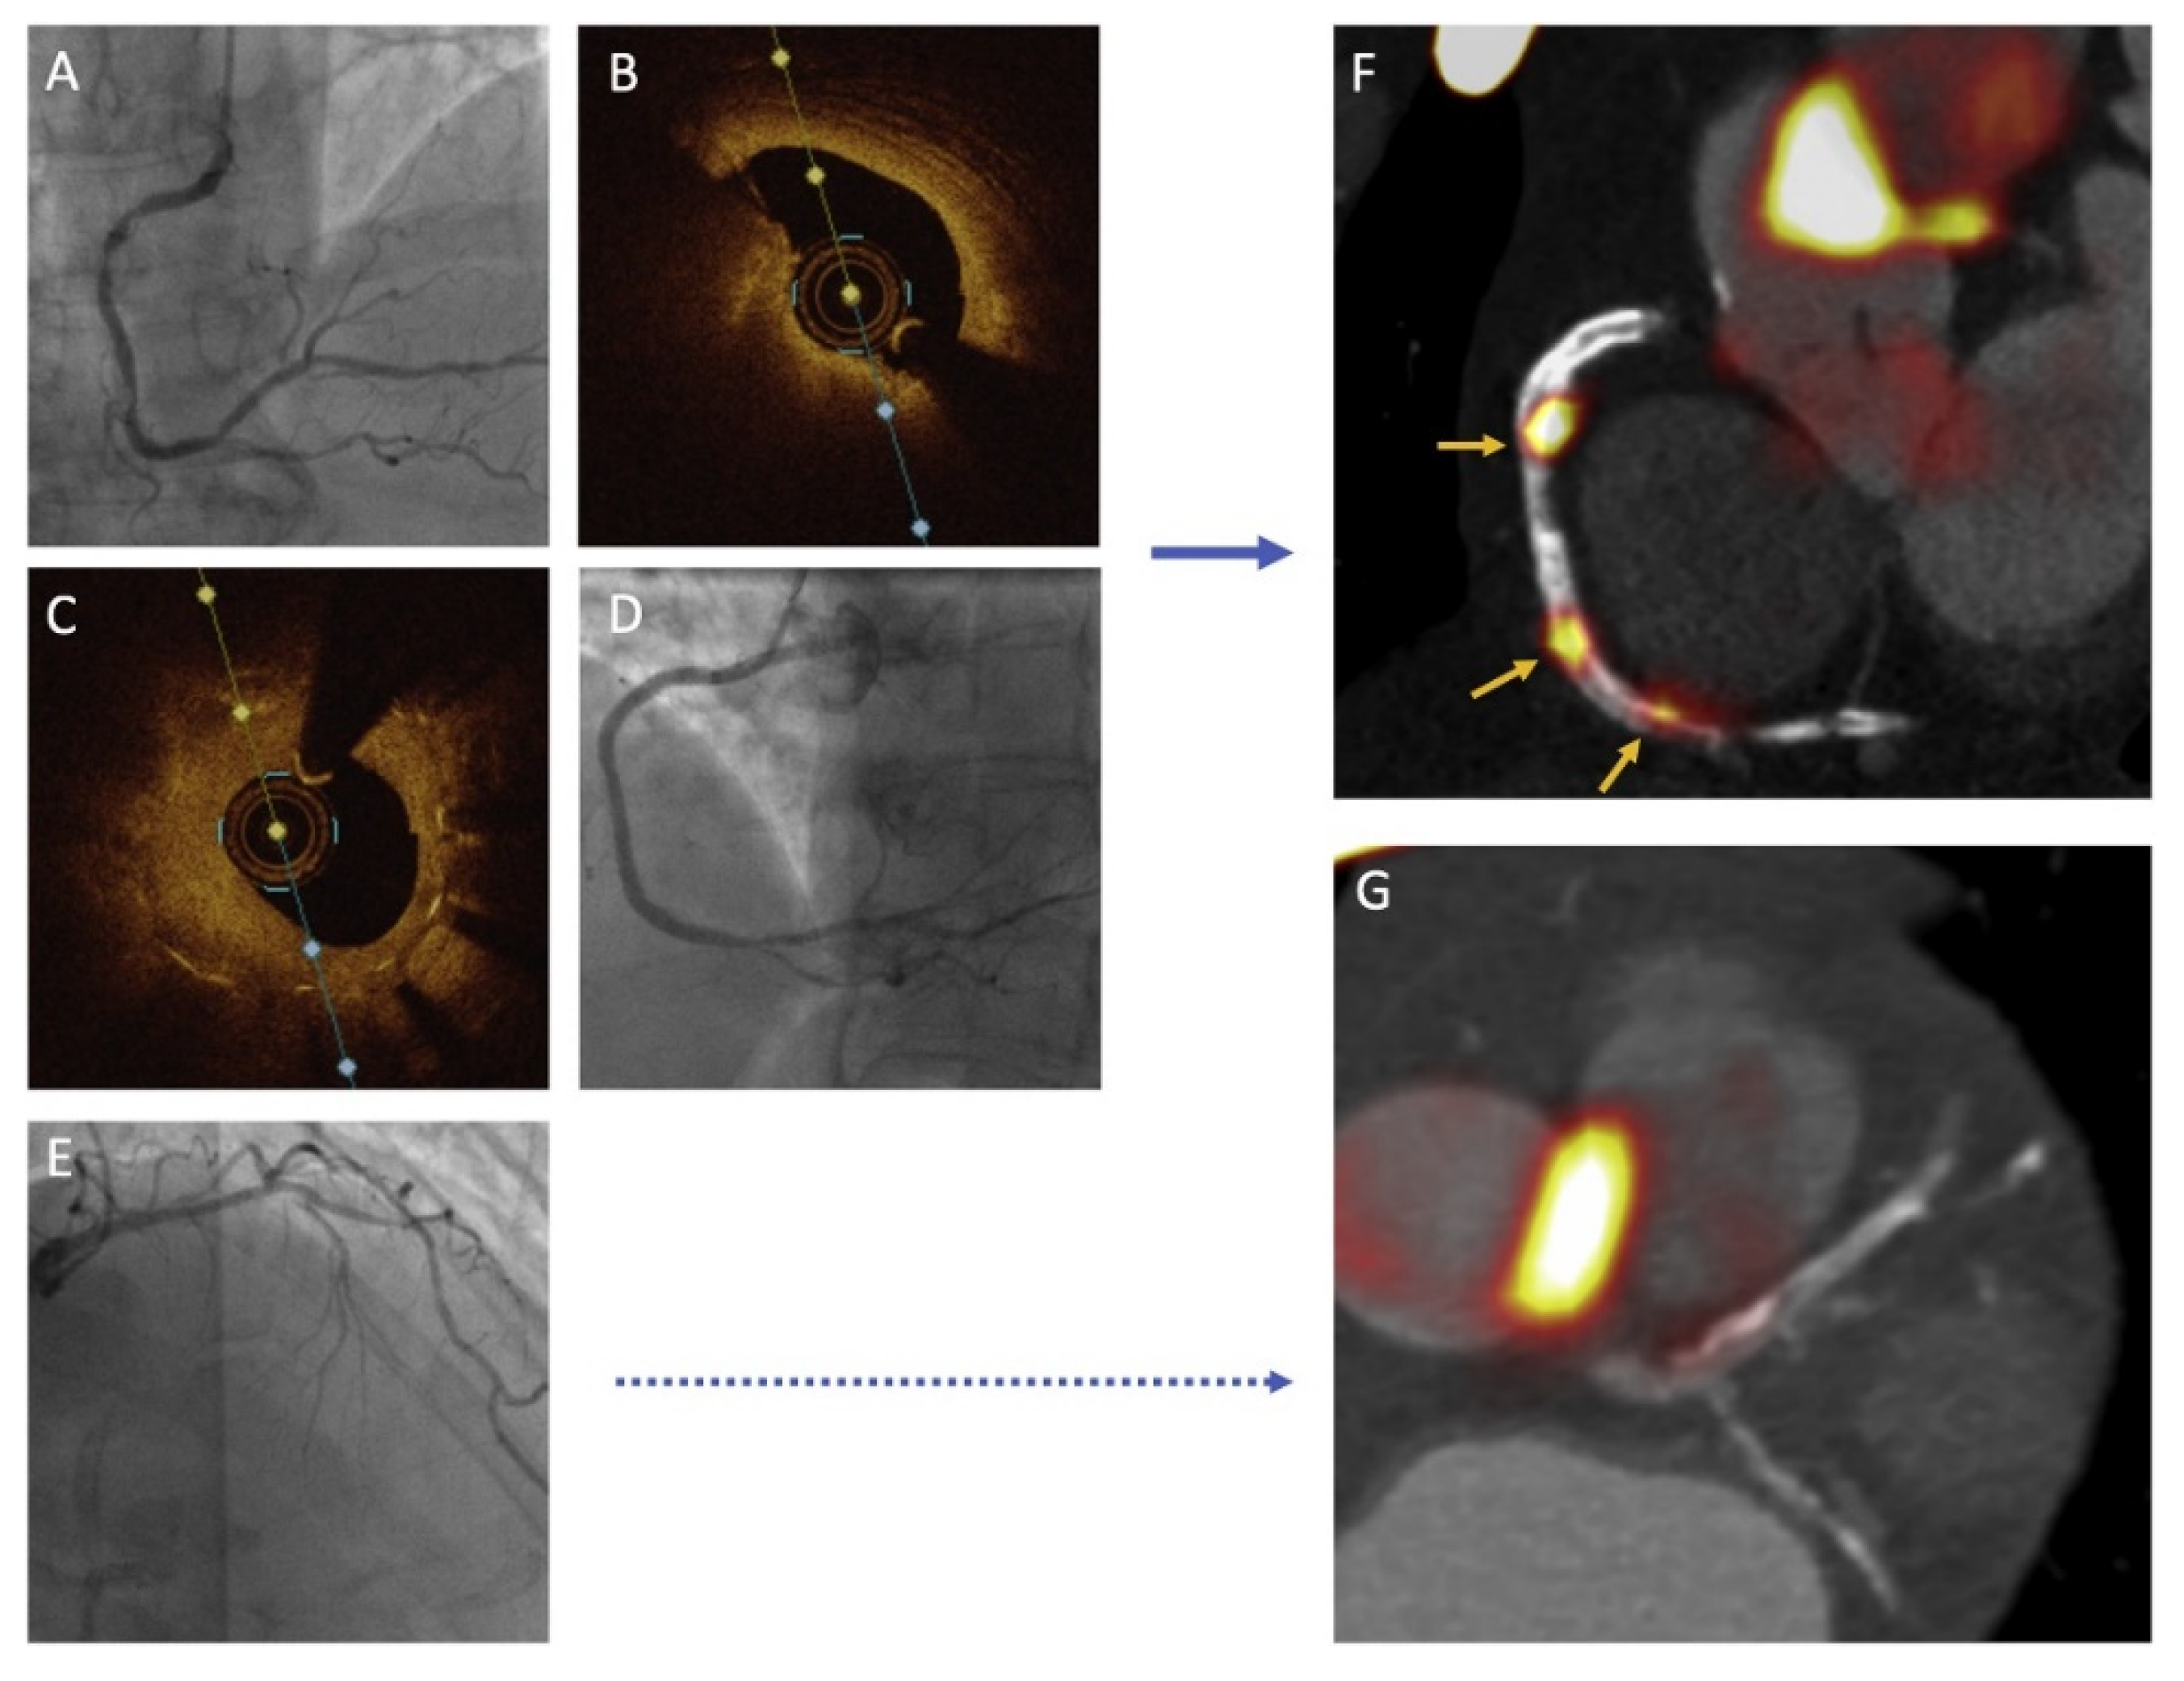

- Bing, R.; Driessen, R.S.; Knaapen, P.; Dweck, M.R. The clinical utility of hybrid imaging for the identification of vulnerable plaque and vulnerable patients. J. Cardiovasc. Comput. Tomogr. 2019, 13, 242–247. [Google Scholar] [CrossRef]

- Giannopoulos, A.A.; Buechel, R.R.; Kaufmann, P.A.; Gaemperli, O. Triple hybrid imaging of a high-risk coronary plaque: Morphology, perfusion, and haemorheology. Eur. Heart J. 2018, 39, 2508. [Google Scholar] [CrossRef]